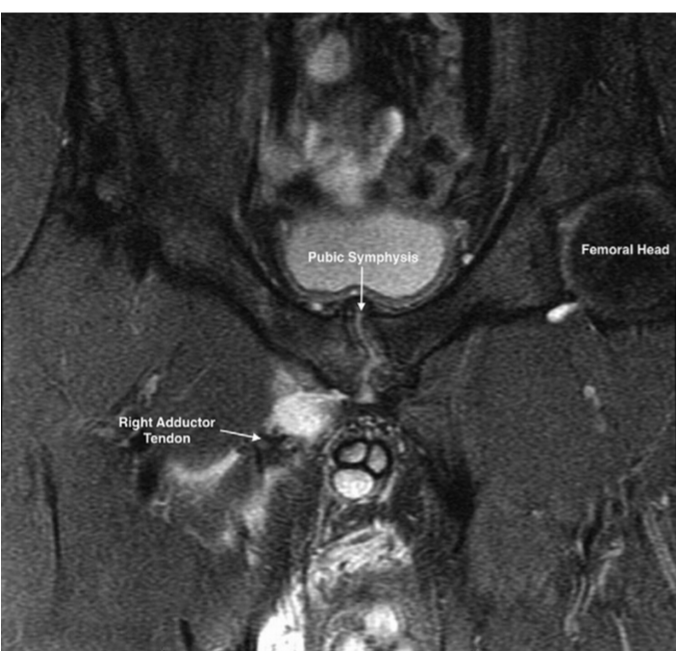

- Adductor level : tendinopathy or avulsion

Adductor tendon avuslion

Arthro- MRI showing the secondary cleft sign